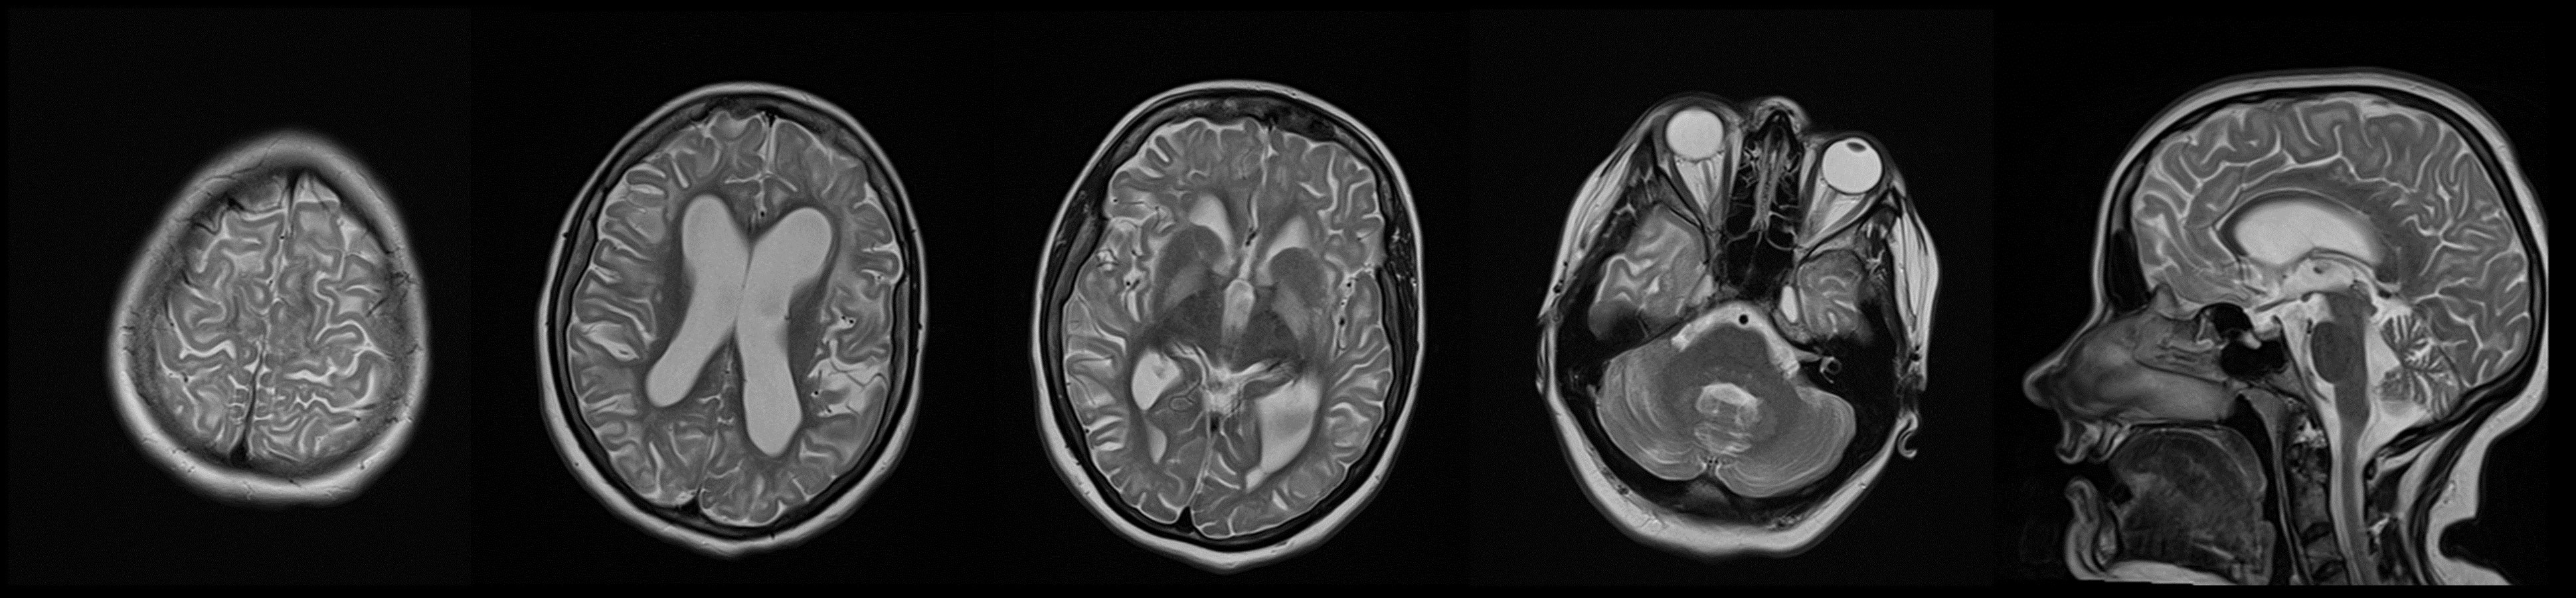

Figure 2

T2-weighted hyperintensity involving the subcortical white matter, globus pallidus, and dentate nucleus of the cerebellum in patient carrying pathogenic variant in L2HGDH gene (Case 2).

Her family history was positive for these disorders and her brother had the same symptoms and died at an early age. At the admission to our center, the neurological examination showed dysarthria, mild head tremor, facial grimacing, anterocollis, dystonia of the hands and feet with mild generalized chorea mainly affecting the trunk (Video 2). In addition, mild dysmetria of the limbs was noted bilaterally. Her gait was wide-based, with a dystonic posture of her left hand and left foot. Brain MRI showed T2-weighted image hyperintensity involving the subcortical white matter, globus pallidus, and dentate nucleus of the cerebellum; these abnormalities were considered highly suggestive of L2HGA (Figure 2). Metabolic screening of urine came back positive for l-2-hydroxy glutaric acid (value was 92 mmol/mol creatinine) using a gas chromatography/mass spectrometer, while normal values are up to 56 mmol/mol creatinine. Clinical exome sequencing revealed homozygous frameshift variant c.114_115del (p. cys38trpfsTer3) in the L2HGDH gene.

Chorea has also been described in other forms of inborn errors of metabolism, such as organic acidurias [3], especially glutaric aciduria type 1, but it is rarely predominant signs and has not been clearly described in L2HGA so far. L2HGA is an AR disorder caused by pathogenic variants in L2HGDH gene encoding a Flavin Adenine Dinucleotide-(FAD)-dependent L-2-hydroxyglutarate dehydrogenase [23]. The disease usually begins in childhood, with macrocephaly, epilepsy, developmental delay, ataxia and involuntary movements [24]. Spasticity, hypotonia and behavioral changes were also mentioned. In the overview of 61 cases, Steenweg et al, described that 38% had movement disorders but without specifying which type they had. Besides limb dystonia, postural tremor and myoclonus, there is a description of writer’s cramp as initial manifestation of L2HGA [24]. We now emphasize that chorea associated with generalized dystonia can also be part of clinical manifestation. Malaquias et al recently expanded L2HGA phenotype and with description of two siblings with atypical parkinsonism and MRI basal ganglia iron deposition [7].

The diagnosis relay on brain MRI pattern as well as high levels of L2-hydroxyglutaric acid level in urine [24]. MRI findings predominantly show T2-weighted hyperintensities involving subcortical white matter sparing the periventricular regions. There are also hyperintense T2-weighted signal changes in the dentate nucleus, globus pallidus and caudate nucleus [25, 26].